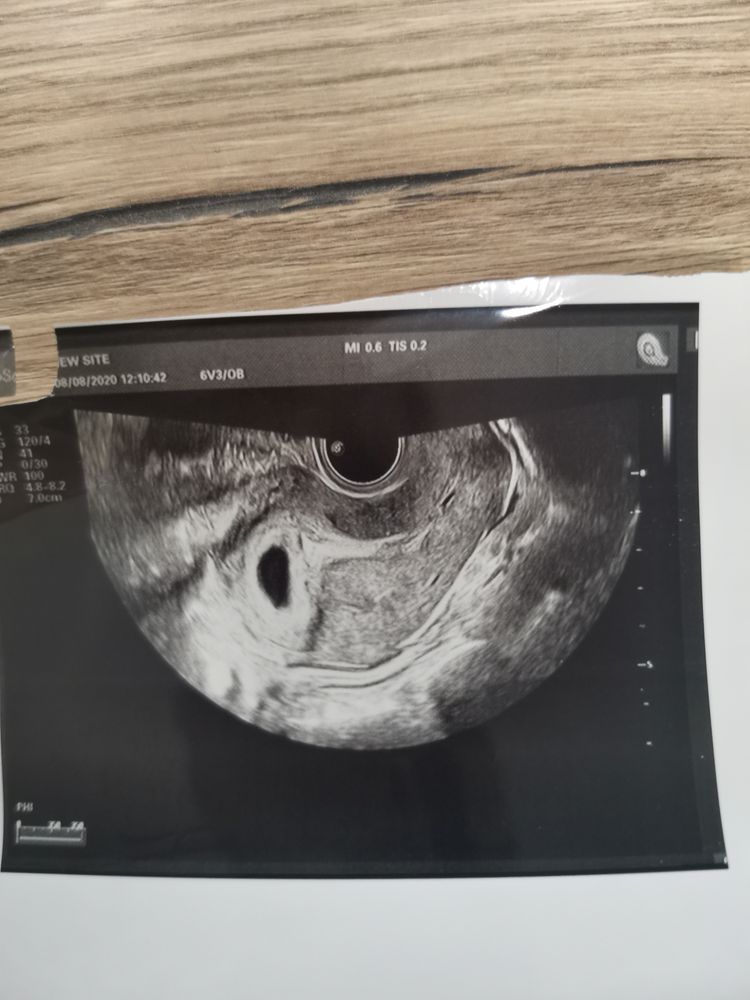

Желточный мешочек крупноват((( она ничего не сказала???

Ирина Герасимова, нет. Важный момент: изменение размеров, формы или плотности желточного мешка имеет значение только в комплексе с другими ультразвуковыми показателями. При выявлении любых отклонений следует оценить состояние эмбриона (локализация, размеры, сердцебиение). Если малыш растет и развивается в соответствии со сроком беременности, не никаких причин для беспокойства. Изменения желточного мешка в данном случае считаются индивидуальной особенностью, не влияющей на течение I триместра.